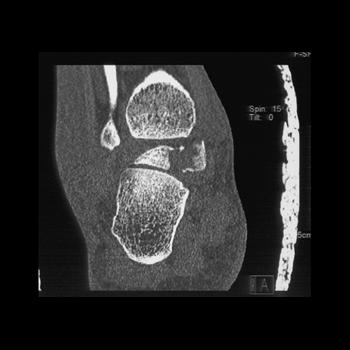

Osteochondral lesions of the talar dome can be challenging to detect with conventional radiographs, and carry a worse prognosis compared to other avulsion fractures. Failure to detect this lesion can result in prolonged disability. In the presence of an ankle joint effusion with no fracture apparent on convential radiograph, CT should be performed if there is a high clinical suspicion for this type of lesion. The most common cause is trauma. Other hypothesized etiologies include ischemic necrosis, spontaneous necrosis, abnormal vascular anatomy and congenital abnormalities.

Osteochondral lesions of the talus are much more common in men (72%). These lesions can occur medially or laterally in the talar dome. The medial lesions occur in the posterosuperior half of the dome of the talus; however, the lateral lesions are situated anterosuperiorly. The lateral lesions almost always follow trauma; however, a history of trauma is presented in only 70% of those with medial lesions.

Treatment depends on the stage of the lesion, as defined by Berndt and Harty. Stage I is defined as a small region of subchondral bone compression. Stage II fractures are incomplete, with partial detachment of the osteochondral fragment. Stage III includes all completely detached but nondisplaced fractures. A displaced, detached fragment constitutes a Stage IV lesion. Stage I-III lesions can be treated by drilling through the sclerotic margin of the lesion in increase perfusion. Intraoperative fluoroscopy has traditionally been used to guide this treatment; however, the utility of computer assisted navigation has recently been reported for preoperative planning.

Fractures of the talar neck are seen in the setting of motor vehicle accidents, falls or direct trauma, as well as other traumatic events that induce an abrupt force from below and dorsiflex the foot. Talar neck fractures are classified by the presence and degree of vertical dislocation. Stage I includes nondisplaced vertical neck fractures. The presence of subtalar dislocation or subluxation equates with a stage II fracture, which usually disrupts 2-3 of the sources of blood supply to the bone. Stages III includes those fractures with subtalar and tibiotalar subluxation or dislocation, and stage IV fractures are vertically displaced with subtalar or tibiotalar subluxation or dislocation, as well as talonavicular subluxation or dislocation. These latter types of injury generally disrupt all 3 sources of blood supply to the talus. Displaced fractures are commonly complicated by ischemia as a result of the blood supply disruption. CT is necessary for proper delineation of the extent of a talar fracture. In addition, CT is very useful for follow up to determine joint alignment, to exclude any residual intrarticular bone fragments and to detect complications of nonunion and osteoarthritis.